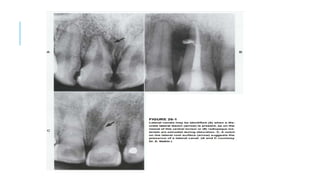

 One of the most frequent bony radiolucencies seen around VRF teeth

radiographic feature of VRF is the “halo” (“J shaped”) appearance.

 This is a combined periapical and lateral radiolucency along the side of the

root, or a lateral radiolucency on one or both sides of the root. Another

typical bony radiolucency is the “angular” type. It is an angular

radiolucency from the crestal bone terminating on the side of the root

 The “angular” radiolucency is more often typical in a case with a “true”

periodontal disease, but as in the previous more “typical” bony

radiolucencies of a VRF tooth, it is only the presence of the

“pathognomonic combination” of clinical signs and symptoms that will

confirm the diagnosis